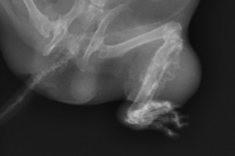

エキゾチックペットの中で特に女の子のウサギは子宮出血や子宮腫瘍の発生などが多くみられる事から避妊手術を受ける事をお勧めしています(子宮疾患についてはケース紹介3参照 )。ウサギの子宮疾患は4歳頃から多発しますが、1歳程度の若齢でも発生がみられます。卵巣子宮摘出術を受ければそれらの発生を未然に防げますが、全身麻酔、入院のストレス、手術そのものの危険性などを乗り越える必要があります。

全身麻酔の危険性は海外のデータでは犬猫が2000頭に1頭亡くなると言われているのに対してウサギは100頭に2頭と言われています。当院ではウサギも内視鏡を用いて気管挿管を行いますが体が小さい場合などはウサギ専用の喉頭マスクを使用し術中に血圧や二酸化炭素濃度、麻酔ガス濃度、酸素飽和度など犬や猫と遜色ないモニターを行うことが出来ます。呼吸停止の際には調節呼吸もできますので、成績は幸いな事にそれよりもはるかに良好です。それでもウサギは犬や猫に比べて心臓や肺の能力が低い為に麻酔の危険性が高いのは確かです。しかしながら、女の子のウサギにおける子宮疾患の発生率の高さと避妊手術の安全性を天秤にかけると、手術を受ける事をお勧めせざるを得ません。